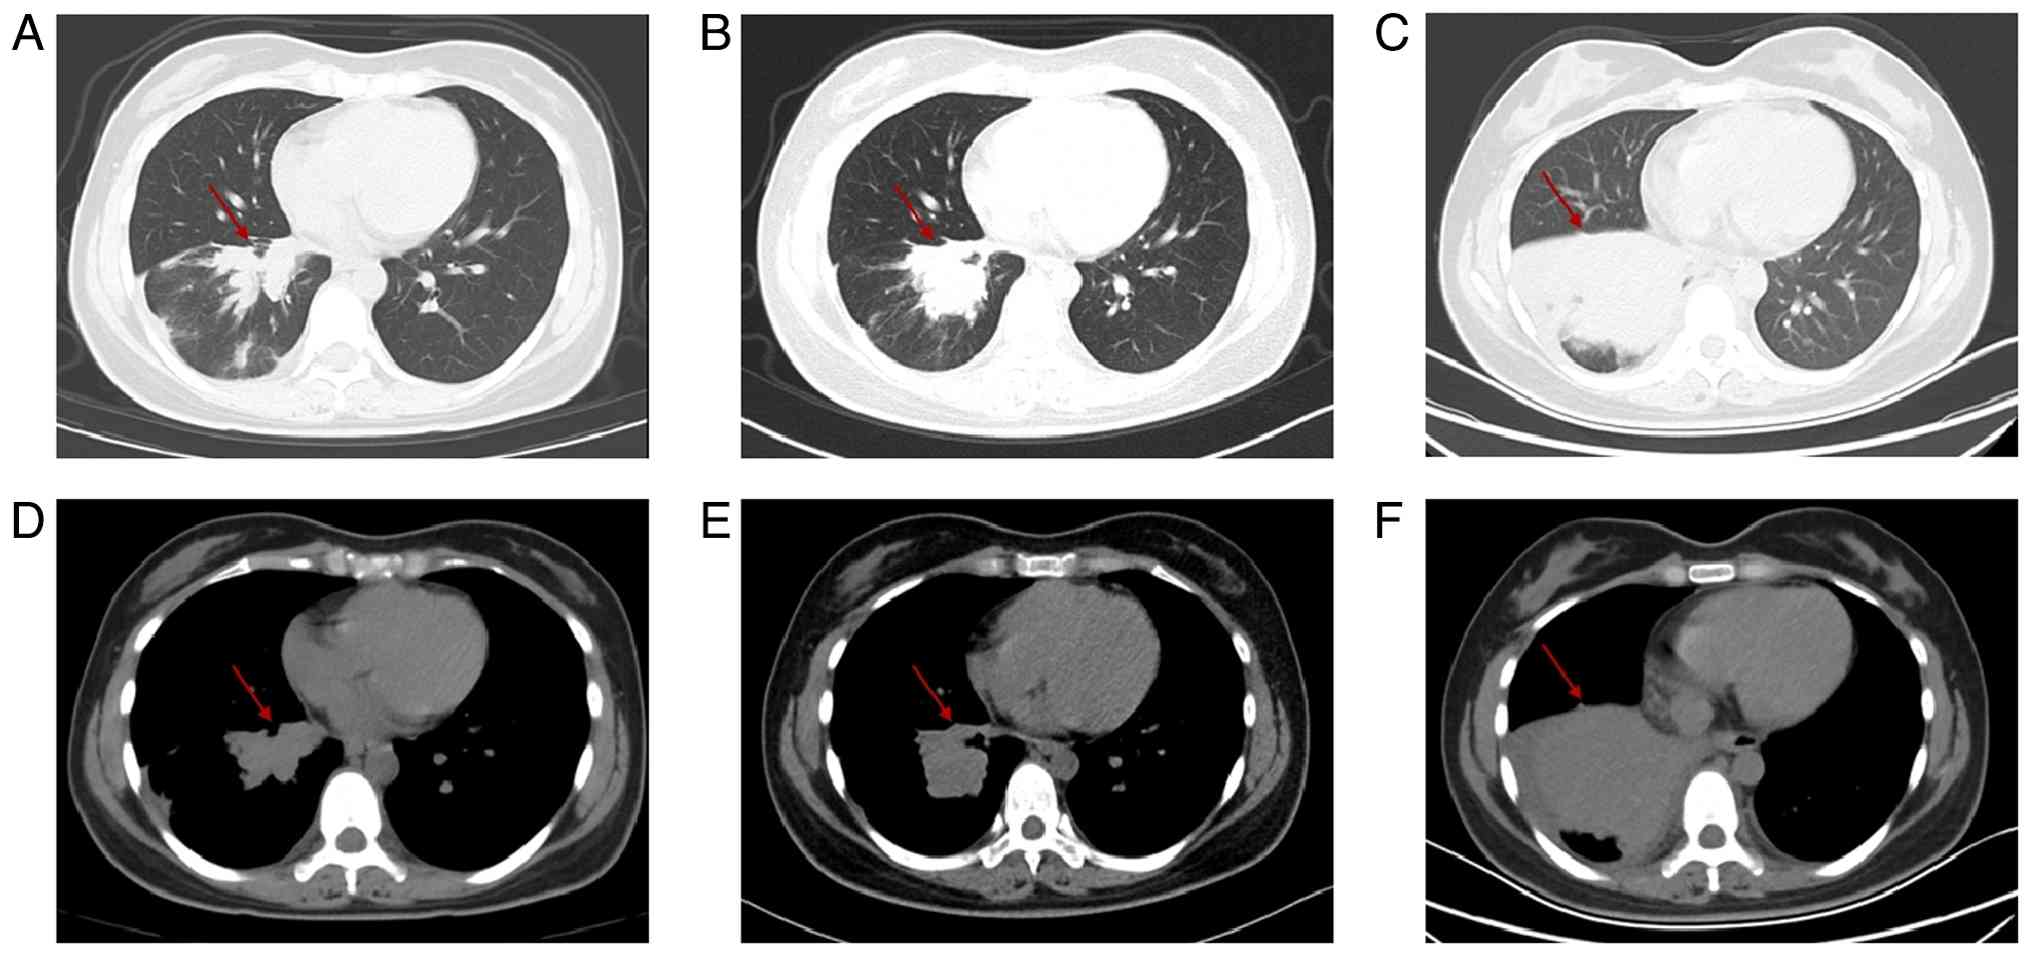

As early as the chest CT scan in January 2024, a soft-tissue mass measuring 3.2×2.5 cm was detected in the lower lobe of the right lung (Fig. 2A and D). However, CT scans of the chest in December 2024 (size, 10×8.4×5.6 cm; Fig. 2C and F) showed that the malignant space in the lower lobe of the right lung was markedly enlarged compared with the previous scan in October 2024 (size, 5.2×3.5 cm; Fig. 2B and E), with multiple ground-glass density nodules of varying sizes in both lungs (the largest diameter of which was ~1.1 cm), multiple enlarged lymph nodes in the right hilar and mediastinal regions, and occlusion of the right lower lung bronchus with obstructive inflammation, as well as thickening of the right lower pleural membrane. Bone destruction of the seventh thoracic vertebra with pathological fracture suggested bone metastasis. CT scans of the abdomen cavity (Fig. 3) showed multiple new lesions in the liver (the largest of which was ~2.7 cm in diameter), suggesting metastases. The imaging suggested that the condition of the patient was in a deteriorating state.

Successive chest CT scans. (A and D)

In January 2024, a soft tissue mass was detected in the lower lobe

of the right lung (size, 3.2×2.5 cm) [(A) lung window; (D)

mediastinal window]. (B and E) In October 2024, the tumor in the

lower lobe of the right lung was found to be slightly enlarged

compared with that in the previous CT scan (size, 5.2×3.5 cm) [(B)

lung window; (D) mediastinal window]. (C and F) In December 2024,

occupation in the lower lobe of the right lung was found to be

markedly enlarged compared with that in the previous CT scan (size,

10×8.4×5.6 cm) [(C) lung window; (F) mediastinal window]. The red

arrows point to the lesion.

Figure 2.

Successive chest CT scans. (A and D) In January 2024, a soft tissue mass was detected in the lower lobe of the right lung (size, 3.2×2.5 cm) [(A) lung window; (D) mediastinal window]. (B and E) In October 2024, the tumor in the lower lobe of the right lung was found to be slightly enlarged compared with that in the previous CT scan (size, 5.2×3.5 cm) [(B) lung window; (D) mediastinal window]. (C and F) In December 2024, occupation in the lower lobe of the right lung was found to be markedly enlarged compared with that in the previous CT scan (size, 10×8.4×5.6 cm) [(C) lung window; (F) mediastinal window]. The red arrows point to the lesion.